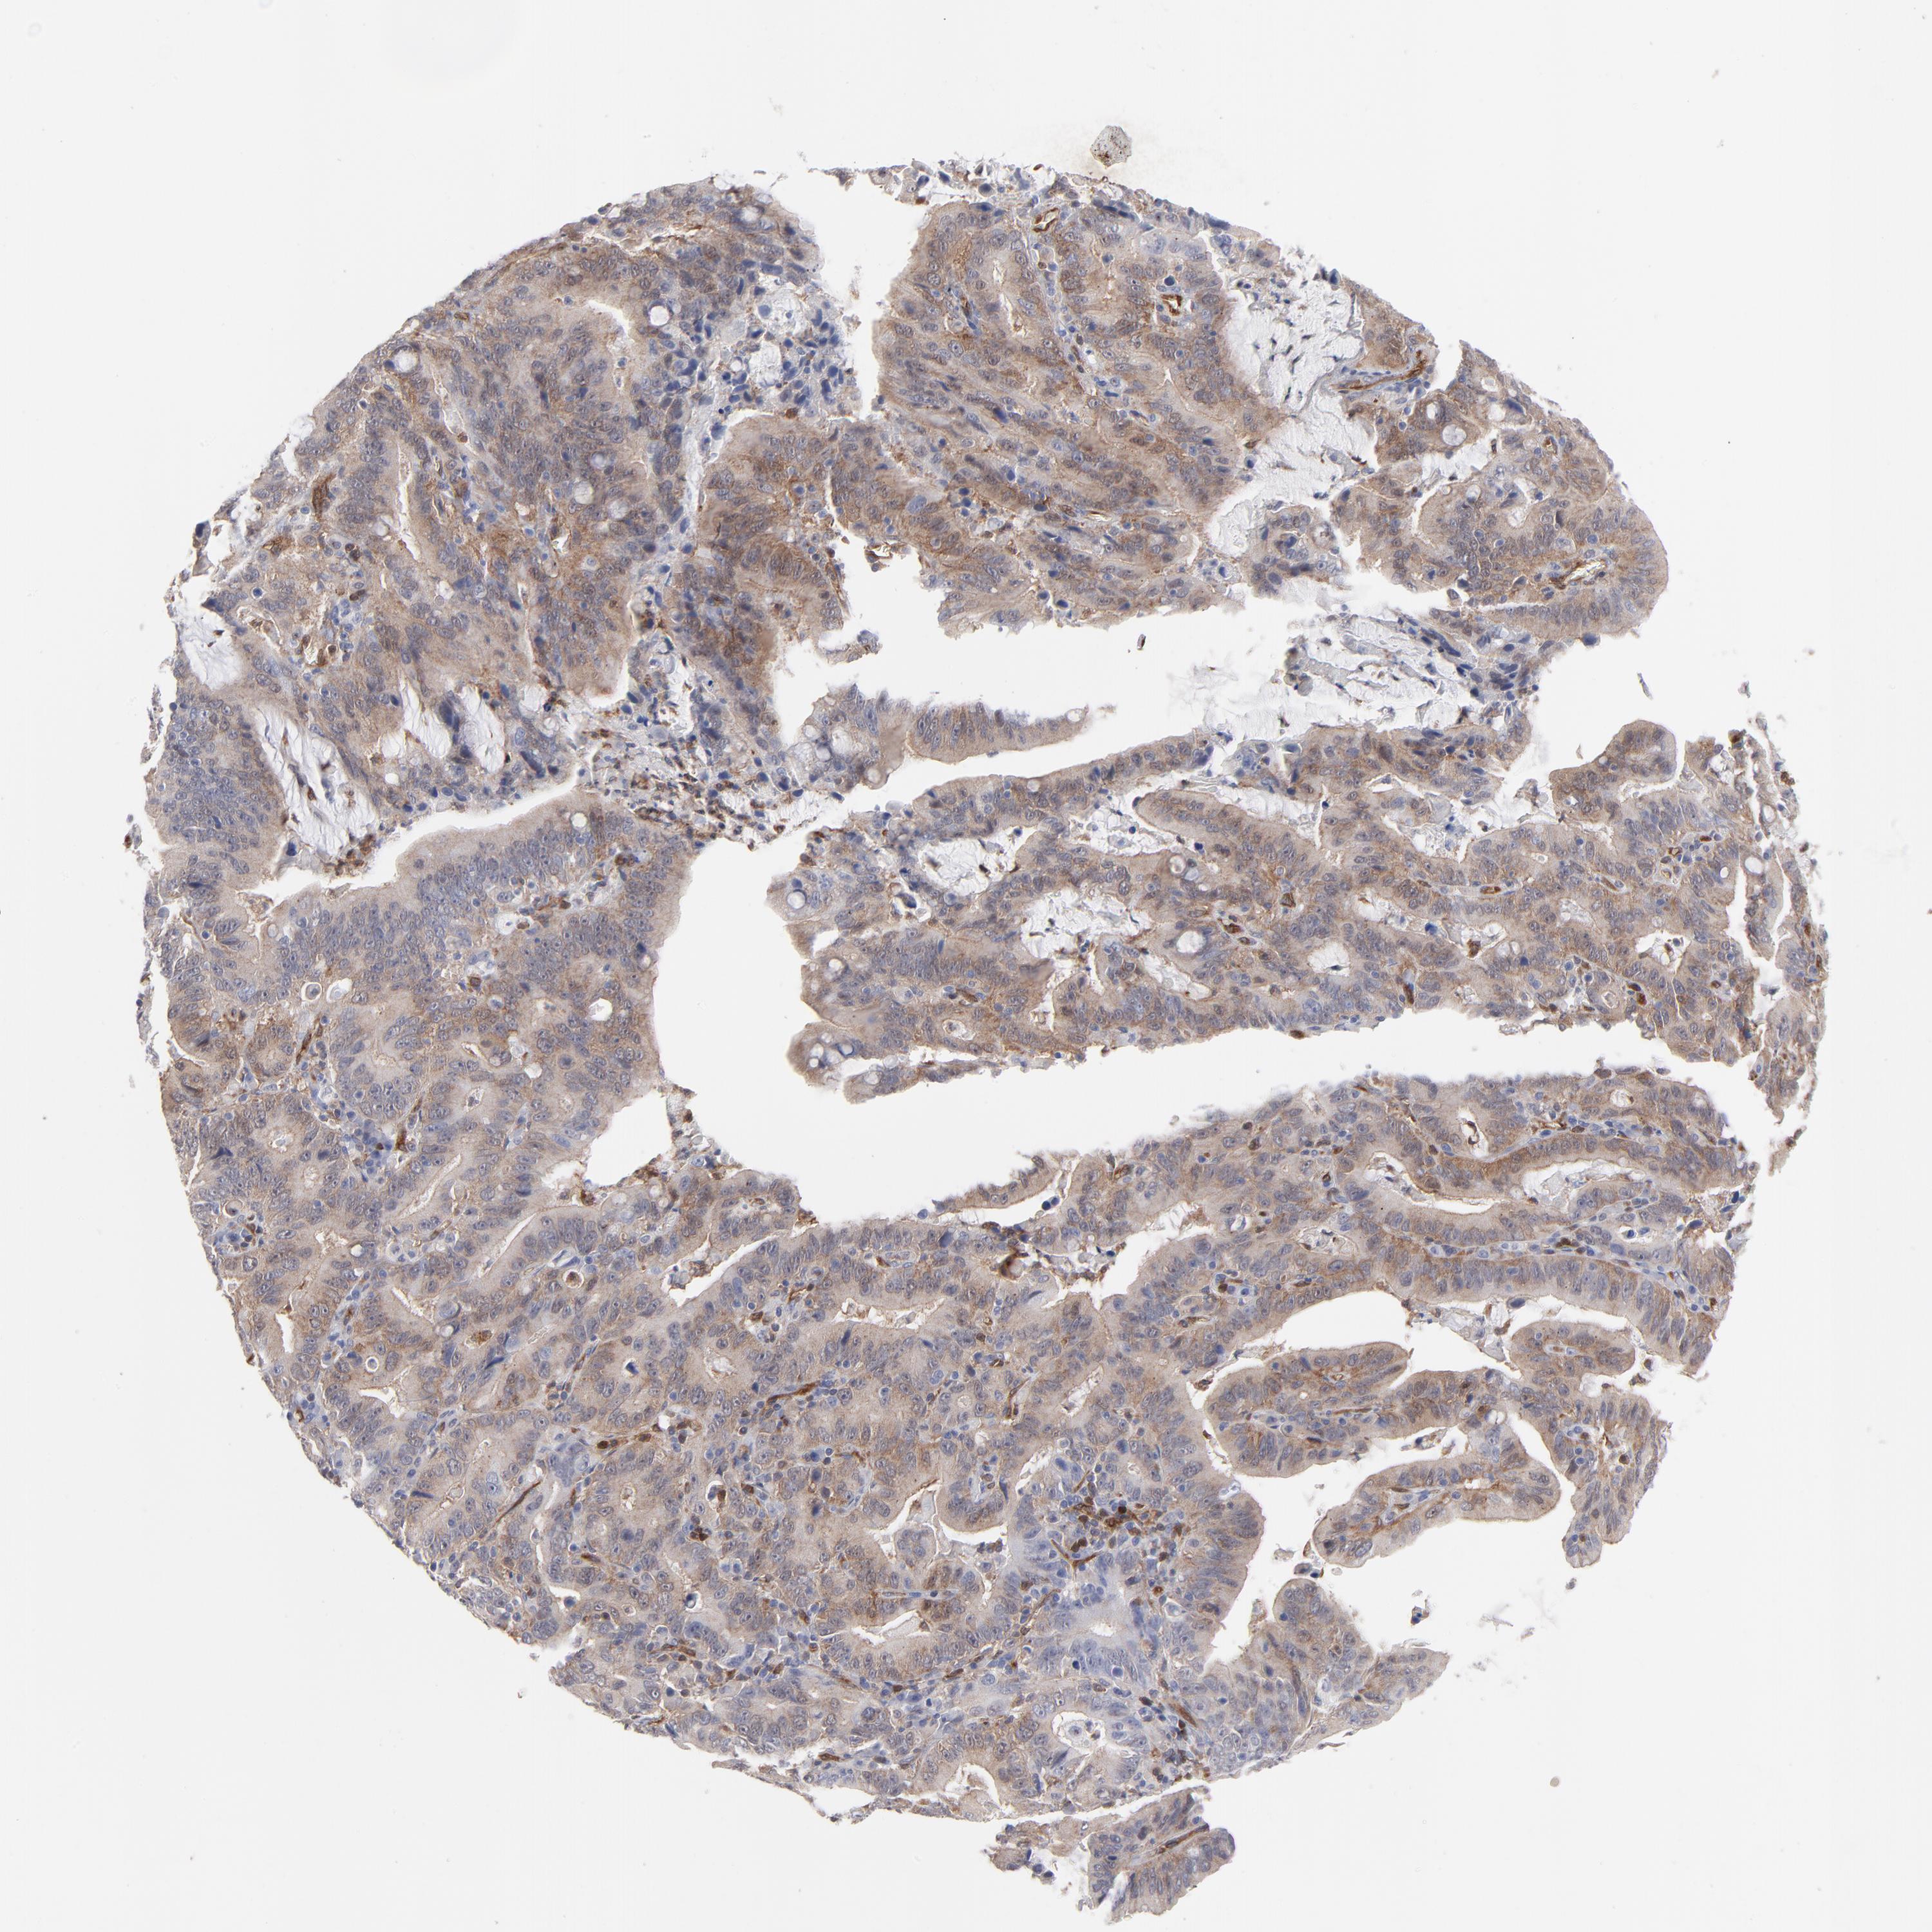

STOMACH CANCER - Protein expressioni

A mouse-over function shows sample information and annotation data. Click on an image to view it in a full screen mode. Samples can be filtered based on level of antibody staining by selecting one or several of the following categories: high, medium, low and not detected. The assay and annotation is described here.

Note that samples used for immunohistochemistry by the Human Protein Atlas do not correspond to samples in the TCGA dataset.

Antibody stainingi

Antibody staining in the annotated cell types in the current human tissue is reported as not detected, low, medium, or high, based on conventional immunohistochemistry profiling in selected tissues. This score is based on the combination of the staining intensity and fraction of stained cells.

Each image is clickable and will lead to virtual microscopy that enables deeper exploration of all samples and also displays staining intensity scores, fraction scores and subcellular localization as well as patient and tissue information for each sample.

Antibody CAB003841

Staining

High

Medium

Low

Not detected

Intensity

Strong

Moderate

Weak

Negative

Quantity

>75%

75%-25%

<25%

None

Location

Nuclear

Cytoplasmic/membranous

Cytoplasmic/membranous,nuclear

Adenocarcinoma, NOS